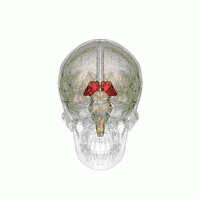

![]() Visual depiction of basic thalamus | |

The thalamus (pl.: thalami; from Greek θάλαμος, "chamber") is a large mass of gray matter on the lateral wall of the third ventricle forming the dorsal part of the diencephalon (a division of the forebrain). Nerve fibers project out of the thalamus to the cerebral cortex in all directions, known as the thalamocortical radiations, allowing hub-like exchanges of information. It has several functions, such as the relaying of sensory and motor signals to the cerebral cortex[1][2] and the regulation of consciousness, sleep, and alertness.[3][4]

The thalami are paired structures of gray matter about four centimetres long and ovoid in appearance,[6] located in the forebrain which is superior to the midbrain, near the center of the brain with nerve fibers projecting out to the cerebral cortex in all directions. In fact, almost all thalamic neurons (with the notable exception of the thalamic reticular nucleus[7]) project to the cerebral cortex, and every region of the cortex so far studied has been found to innervate the thalamus.[8]